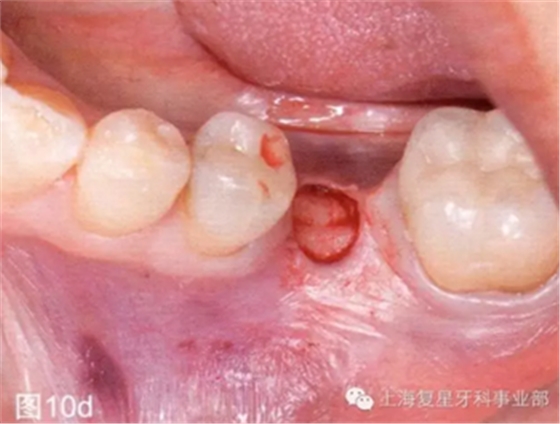

第二天患者就診進行手術(shù)。用0.12%葡萄糖酸氯已定漱口水(Oralgene,Laboratorios Maver)含漱2分鐘后,進行消毒和術(shù)區(qū)的準(zhǔn)備,在缺牙區(qū)(36#牙區(qū)域)的頰舌側(cè)和頂部進行局部麻醉(2%鹽酸利多卡因和1:100000腎上腺素)。幾分鐘后,置入外科導(dǎo)板,在外科導(dǎo)板上的孔洞中置入中空的圓柱形金屬引導(dǎo)管,然后引導(dǎo)軟組織打孔器進入,其轉(zhuǎn)速為1200rpm。然后去除引導(dǎo)板,用剝離子去除截面的軟組織,并浸泡在鹽溶液中(圖10b-d)。

圖10d:去除剝離的軟組織